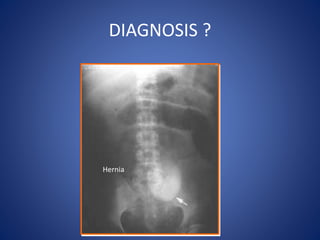

DIAGNOSIS ?

Hernia

Paralytic Ileus

DIAGNOSIS

Small bowel obstruction

Large bowel obstruction